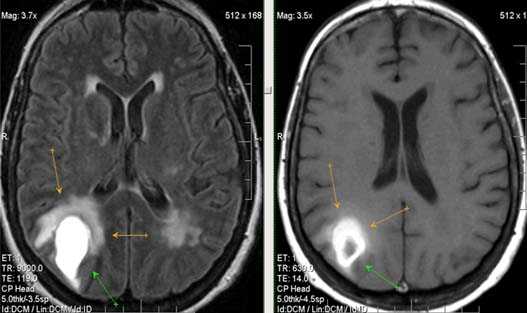

Выраженная сосудистая энцефалопатия с наличием множественных очагов хронической ишемии, лакунарных постишемических кист. Программа ДВИ четко показывает фокус острого ОНМК в базальных ядрах справа на фоне лейкодистрофии.

Ишемической инсульт в бассейне левой средней мозговой артерии. Отсутствие феномена пустоты потока на уровне интракраниального отдела левой ВСА (признаки замедления кровотока).

Ишемический инсульт в ВББ слева. Отсутствие феномена пустоты потока на уровне экстракраниального отдела левой позвоночной артерии (признаки замедления кровотока).

Постишемическая лакунарная киста с перифокальным глиозом (средняя треть corona radiata справа)

Характерным проявлением ДЭП на МР-томограммах является наличие множественных очагов глиоза.

В белом веществе левой лобной и обеих теменных долей, преимущественно субкортикально, выявлены множественные мелкие очаги хронической ишемии (большинство локализованных в бассейне правой средней мозговой артерии).

Проявлением хронической ишемии является также развитие выраженных дистрофических изменений белого вещества паравентрикулярной локализации - лейкоареоз.

Выраженные дистрофические изменения белого вещества паравентрикулярной локализации - лейкоареоз.

Сочетание мультифокальных очаговых изменений с диффузной кортикальной церебральной атрофией.